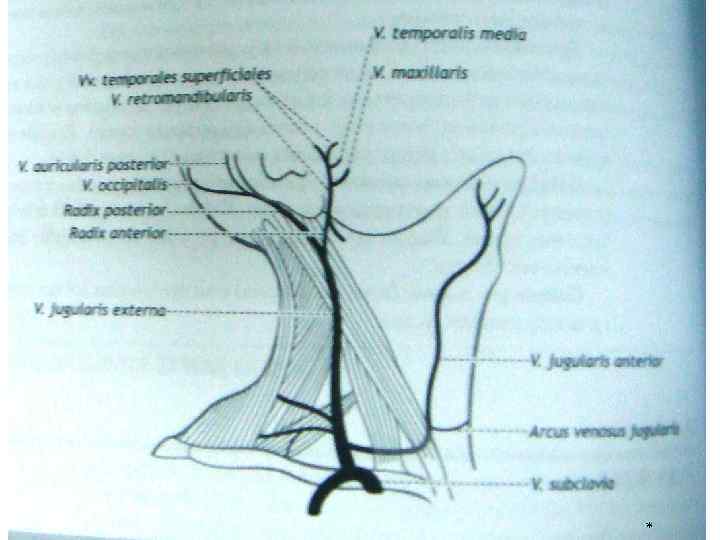

Анатомия внутренней яремной вены: КТ изображения